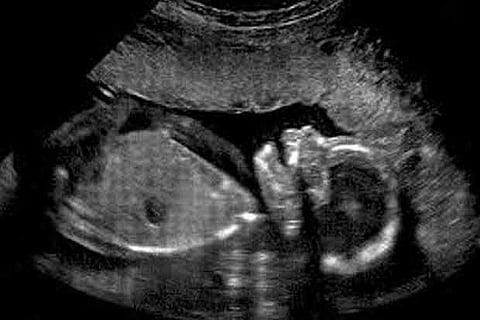

Arun Dhandapani retired from the Sivaganga Medical College Hospital. Later, he started a private hospital with an attached scan centre. There were complaints that he had been revealing the sex of the foetus to the parents and had been making money.

As the practice of revealing the sex of the foetus is a crime under Pre-natal Diagnostic Techniques (Regulation and Prevention of Misuse) Act of 1994, there were several complaints lodged with the District Health Department about him.

An expert committee of three members in the rank of Joint Directors were formed and the team comprising Sivaganga JD Vijayan Madhamadakki, Madurai JD Rukmani, Chennai JD Gurunathan inspected the hospital on Thursday. They found the complaints to be true and the team also noticed that the person operating the scan centre was not trained. They sealed both the scan centre and the hospital.